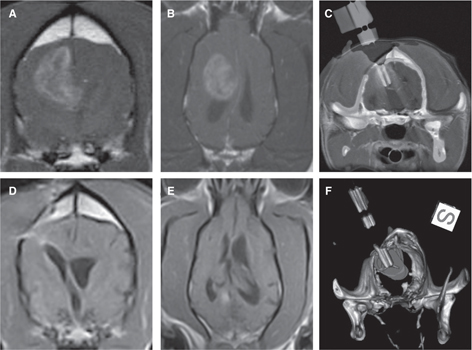

We have evaluated the safety and preliminary efficacy both IRE (Figure 3) and H-FIRE (Figure 4) in dogs with spontaneous brain tumors (77, 79, 86). An integral component of the preclinical evaluation of IRE and H-FIRE was the development of anatomically accurate numerical treatment planning models that maximize tumor coverage while minimizing damage to surrounding healthy tissue and also account for the increase in tissue conductivity that occurs during pulse delivery (86–88). Incorporating therapeutic plans developed from patient-specific, segmented medical images imported into finite element analysis modeling software, we have confirmed the ability of IRE and H-FIRE to safely and precisely ablate normal and neoplastic canine brain tissues with a submillimeter line of demarcation between ablated and non-treated tissues (79, 86, 89). IRE treatment of canine gliomas resulted in significant objective tumor responses in 4/5 dogs with quantifiable target lesions (Figure 3), and these radiographic responses were accompanied by improvements in Karnofsky performance scores and posttreatment seizure control (72, 86). Similarly, using a treat and resect treatment paradigm, we have confirmed the ability of H-FIRE to safely and precisely ablate clinically relevant volumes of canine brain tumors without the induction of muscular contractions during pulse delivery (Figure 4).

Figure 3 Stereotactic glioblastoma ablation with irreversible electroporation (IRE). Pretreatment transverse (A) and dorsal planar (B) post-contrast T1-weighted MR demonstrating ring-enhancing glioblastoma in the frontoparietal lobe of the cerebrum. Co-registered intraoperative CT and pre-treatment MR images (C) and three-dimensional reconstructed CT (F) with IRE electrodes in situ within the tumor in preparation for ablation. Three-month post-IRE treatment transverse (D) and dorsal planar (E) post-contrast T1-weighted MR illustrating 95% reduction in tumor burden.